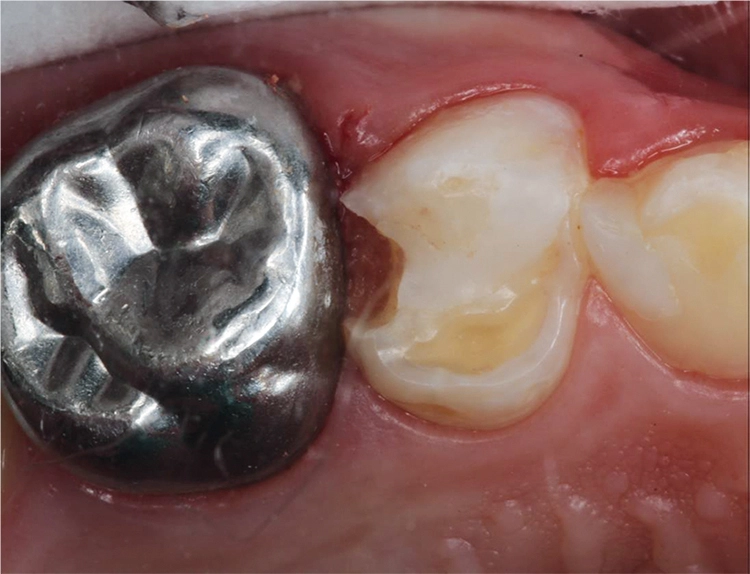

Bei einem Kontrolltermin eines 8-jährigen Jungen imponierte eine insuffiziente Füllung im linken Oberkiefer (Abb. 1). Die Anfertigung eines halbseitigen Orthopantomogramms (OPG) zeigte eine koronale Aufhellung an Zahn 64 distal (Abb. 2). Aufgrund der vollständigen mesialen Wurzel entschied man sich für den Erhalt des Zahnes 64 und eine Restauration mit einem plastischen Füllungsmaterial.

Möhn, KrämerHierfür wurde die Kavität zunächst mit einem birnenförmigen Diamanten aufgezogen und das kariöse Dentin mit einem Polymerbohrer schonend exkaviert (Abb. 3). Für die Formgebung und den Schutz des Nachbarzahnes wurde das Teilmatrizensystem Palodent® V3 verwendet (Abb. 4). Im Anschluss folgte die Füllungstherapie mittels Surefil one™ in Farbe A2.